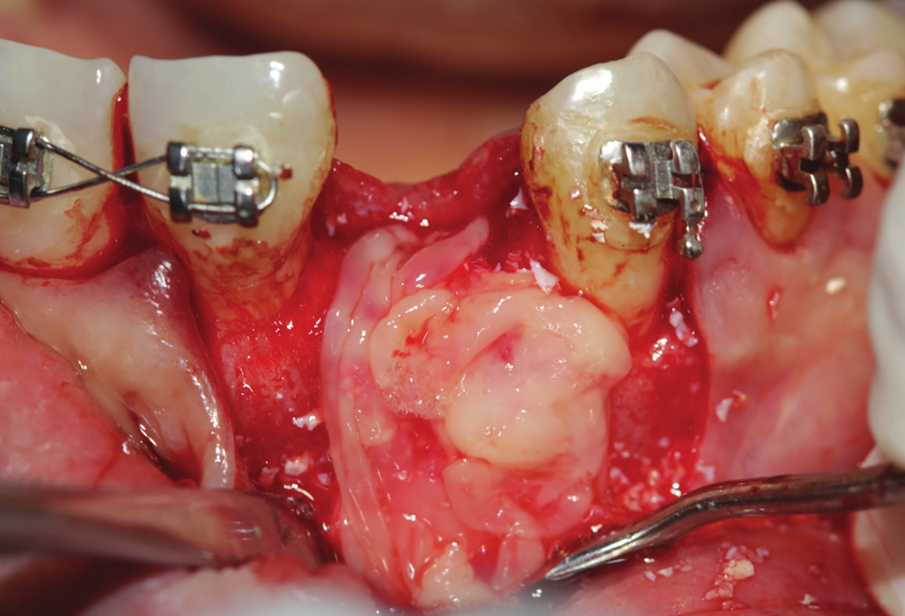

Figure 24: Bone cavity showing extended bone loss.

A 38 years-old female patient came to our clinic with swelling upper anterior area, she was medically fit with no health problems. The patient underwent an orthodontic treatment for 2 years and was about to remove it and place retainer. Intraoral examination showed swelling apical area of tooth no 7. The periapical x-ray and CAT view revealed a lateral perforation on the same mentioned tooth with a well circumscribed radiolucency in apical area (Fig.20, 21). Pain on percussion and slight mobility were noted. A surgical enucleation and extraction of tooth no 7 were conducted (Fig.22, 23, 24). 3 months postoperative CAT view shows an advanced horizontal bone loss with no recurrence of lesion in the area (Fig. 26), clinically after reflection of mucoperiosteal flap, the situation confirmed the CAT image (Fig.25) , the case was planned for PRF -associated bovine bone technique replacing the aggressive autologous bone graft procedure. After collection of PRF from patient blood culture, a first layer of L-PRF covering the bovine bone associated PRF complex (sticky bone) was done (Fig.27). The second layer of L-PRF came to cover the cross-linked collagen membrane (Fig. 28).